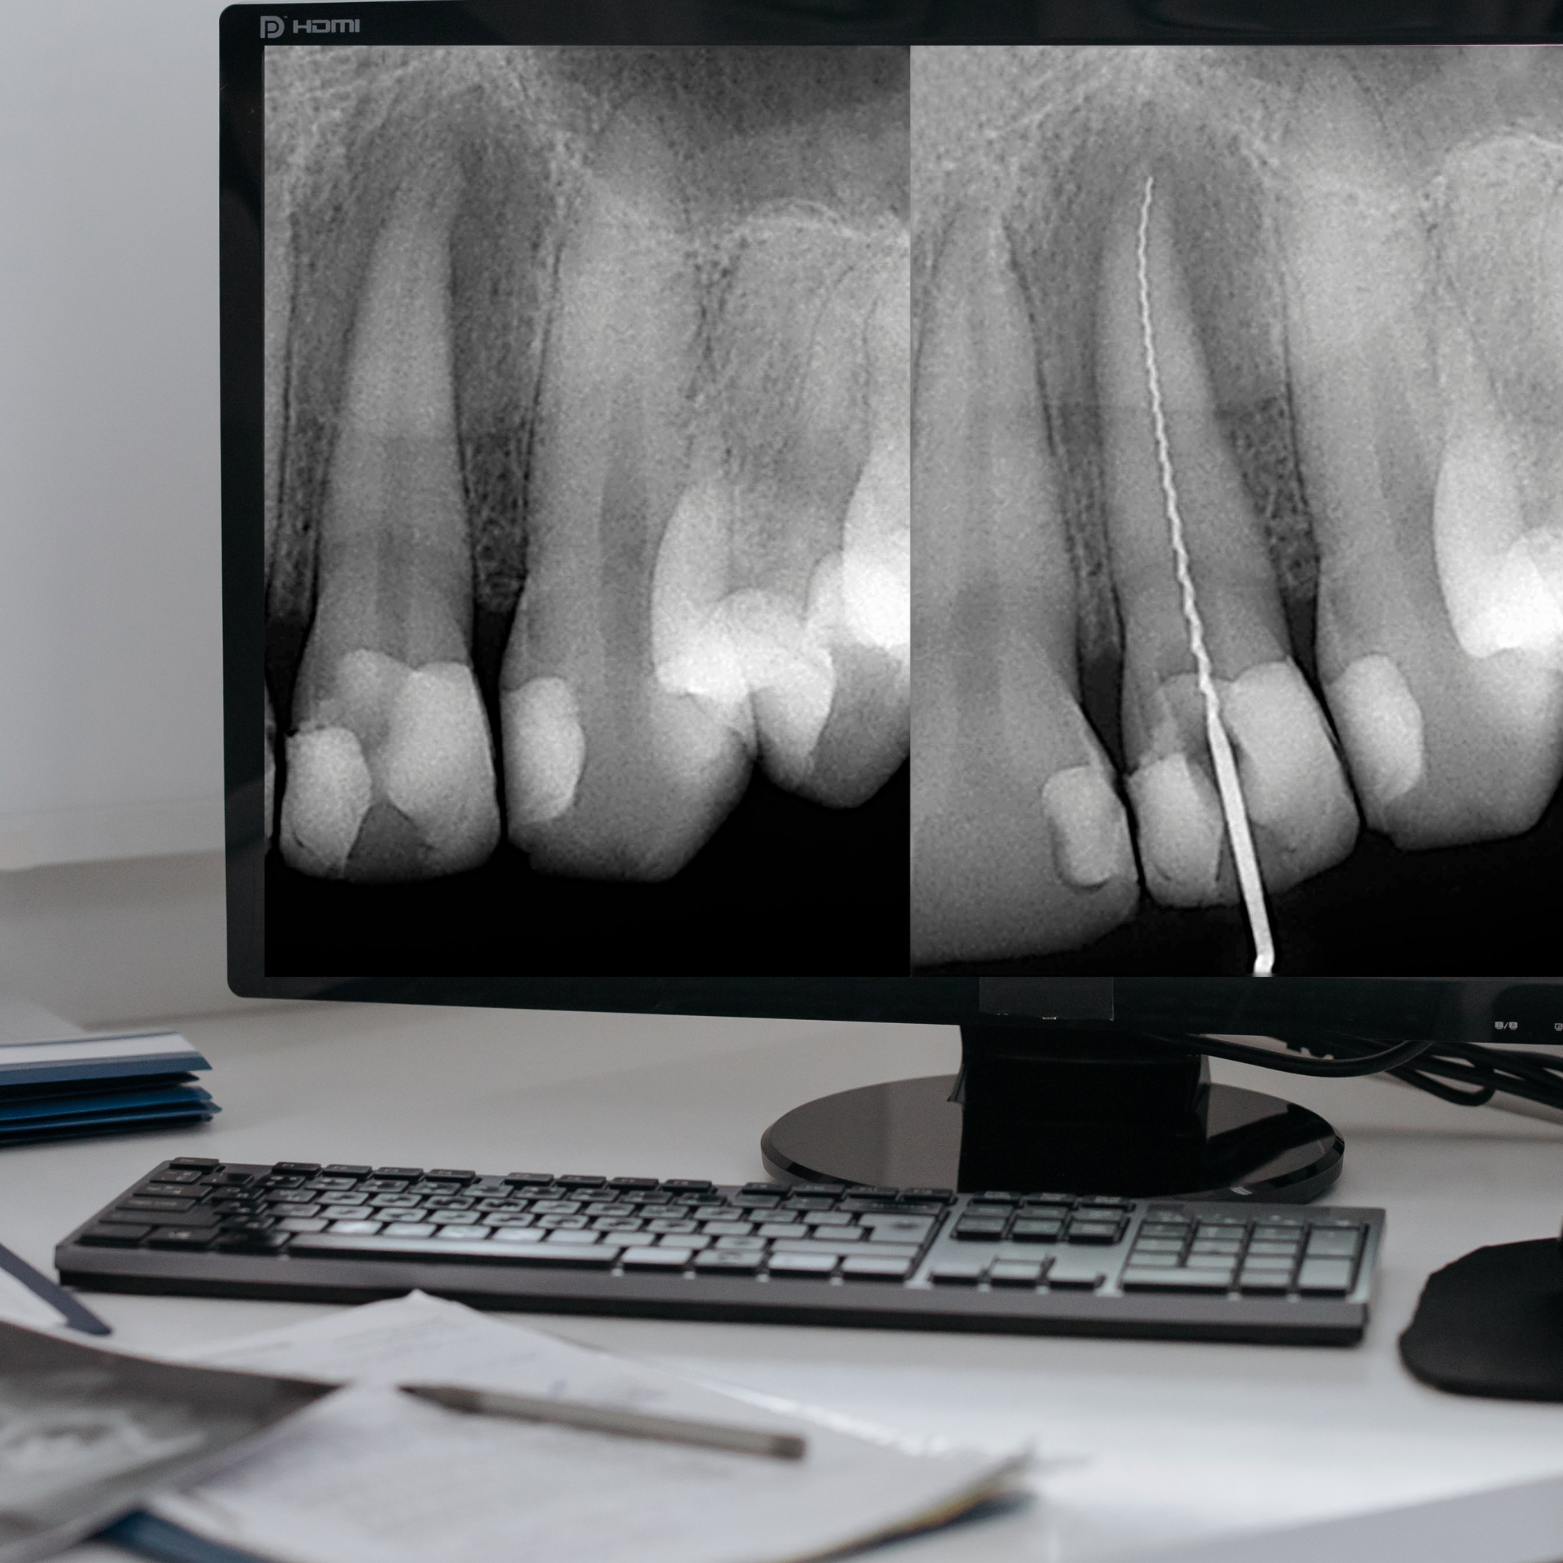

INTRAORAL X-RAY

High-quality Intraoral X-rays reveal the fine details beneath the gum-line, bone and tooth surfaces that the naked eye cannot detect, helping ensure accurate diagnoses and reducing the risk of missed important information.

With precise imaging, our clinicians can identify decay, bone loss, root issues, and hidden infections early, allowing for targeted treatment plans and greater peace of mind.

Your safety is our top priority: we adhere to strict radiation protection standards and use modern, low-dose equipment and shielding protocols to minimize exposure while delivering the diagnostic clarity you deserve.